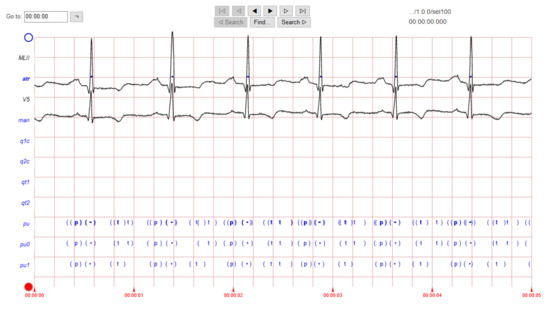

The ECG images that were used as data input for the CNN were obtained from an open-source database, namely, the QT Database from the PhysioNet [28]. An example of ECG images, i.e., ‘normal’, ‘sudden death’, ‘arrhythmia’, and ‘supraventricular arrhythmia’, waveform is presented in Figure 1, Figure 2, Figure 3 and Figure 4. These data were preprocessed prior to building a CNN model for ECG classification and prediction. Four classifications have been selected from several patients, with multiple images taken from each patient. Images were manually cropped from one recording signal that consist of one complete pulse (P wave, QRS complex, and T wave), with the exceptions of cardiac abnormality categories, where certain visual features may be absent. The objective of the cropping is to simulate the camera capture during the development of the online and real-time ECG signal classification and prediction presented in Section 5.

Figure 1.

ECG image data for ‘normal sinus’ waveform.